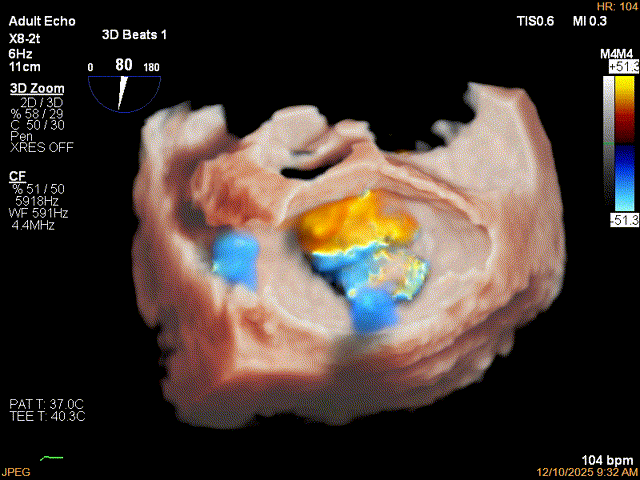

为了避免长时间TEE对食道造成损伤,术前即刻3D-TEE短时进一步明确二尖瓣病变相关解剖情况。

术前3D

术前3Dcolor

3D-TEE二尖瓣相关解剖学参数:后叶长度:22-25mm,前叶长度:31-34mm;瓣环AP径:47mm,ML径:48mm;瓣口面积:约7.8cm²;脱垂宽度:30mm,最大连枷间距:14mm。

四条肺静脉均可测及收缩期反向血流

术前即刻TEE进一步明确了二尖瓣反流的机制(DMR)及反流程度(5+),重点完善了病变区域二尖瓣解剖结构的评估,预估手术难点/影响手术效果的解剖结构为冗长的二尖瓣后叶(PML约25mm),宽大的脱垂(Flail Width约30mm),超大的连枷间距(Flail gap约14mm)。